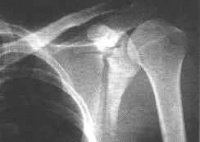

肩胛骨骨折

影像学表现]

肩胛骨骨折可分为肩胛骨体部骨折肩胛颈部骨折、肩胛盂骨折、喙突骨折肩峰骨折。肩胛骨体部骨折是肩胛骨骨折的常见类型,多为粉碎性骨折,肩胛骨体部骨折线可为斜行、纵行或星形,亦可贯通至肩胛岗。由于肩胛骨被肌肉筋膜紧紧包裹,骨折移位多不明显。